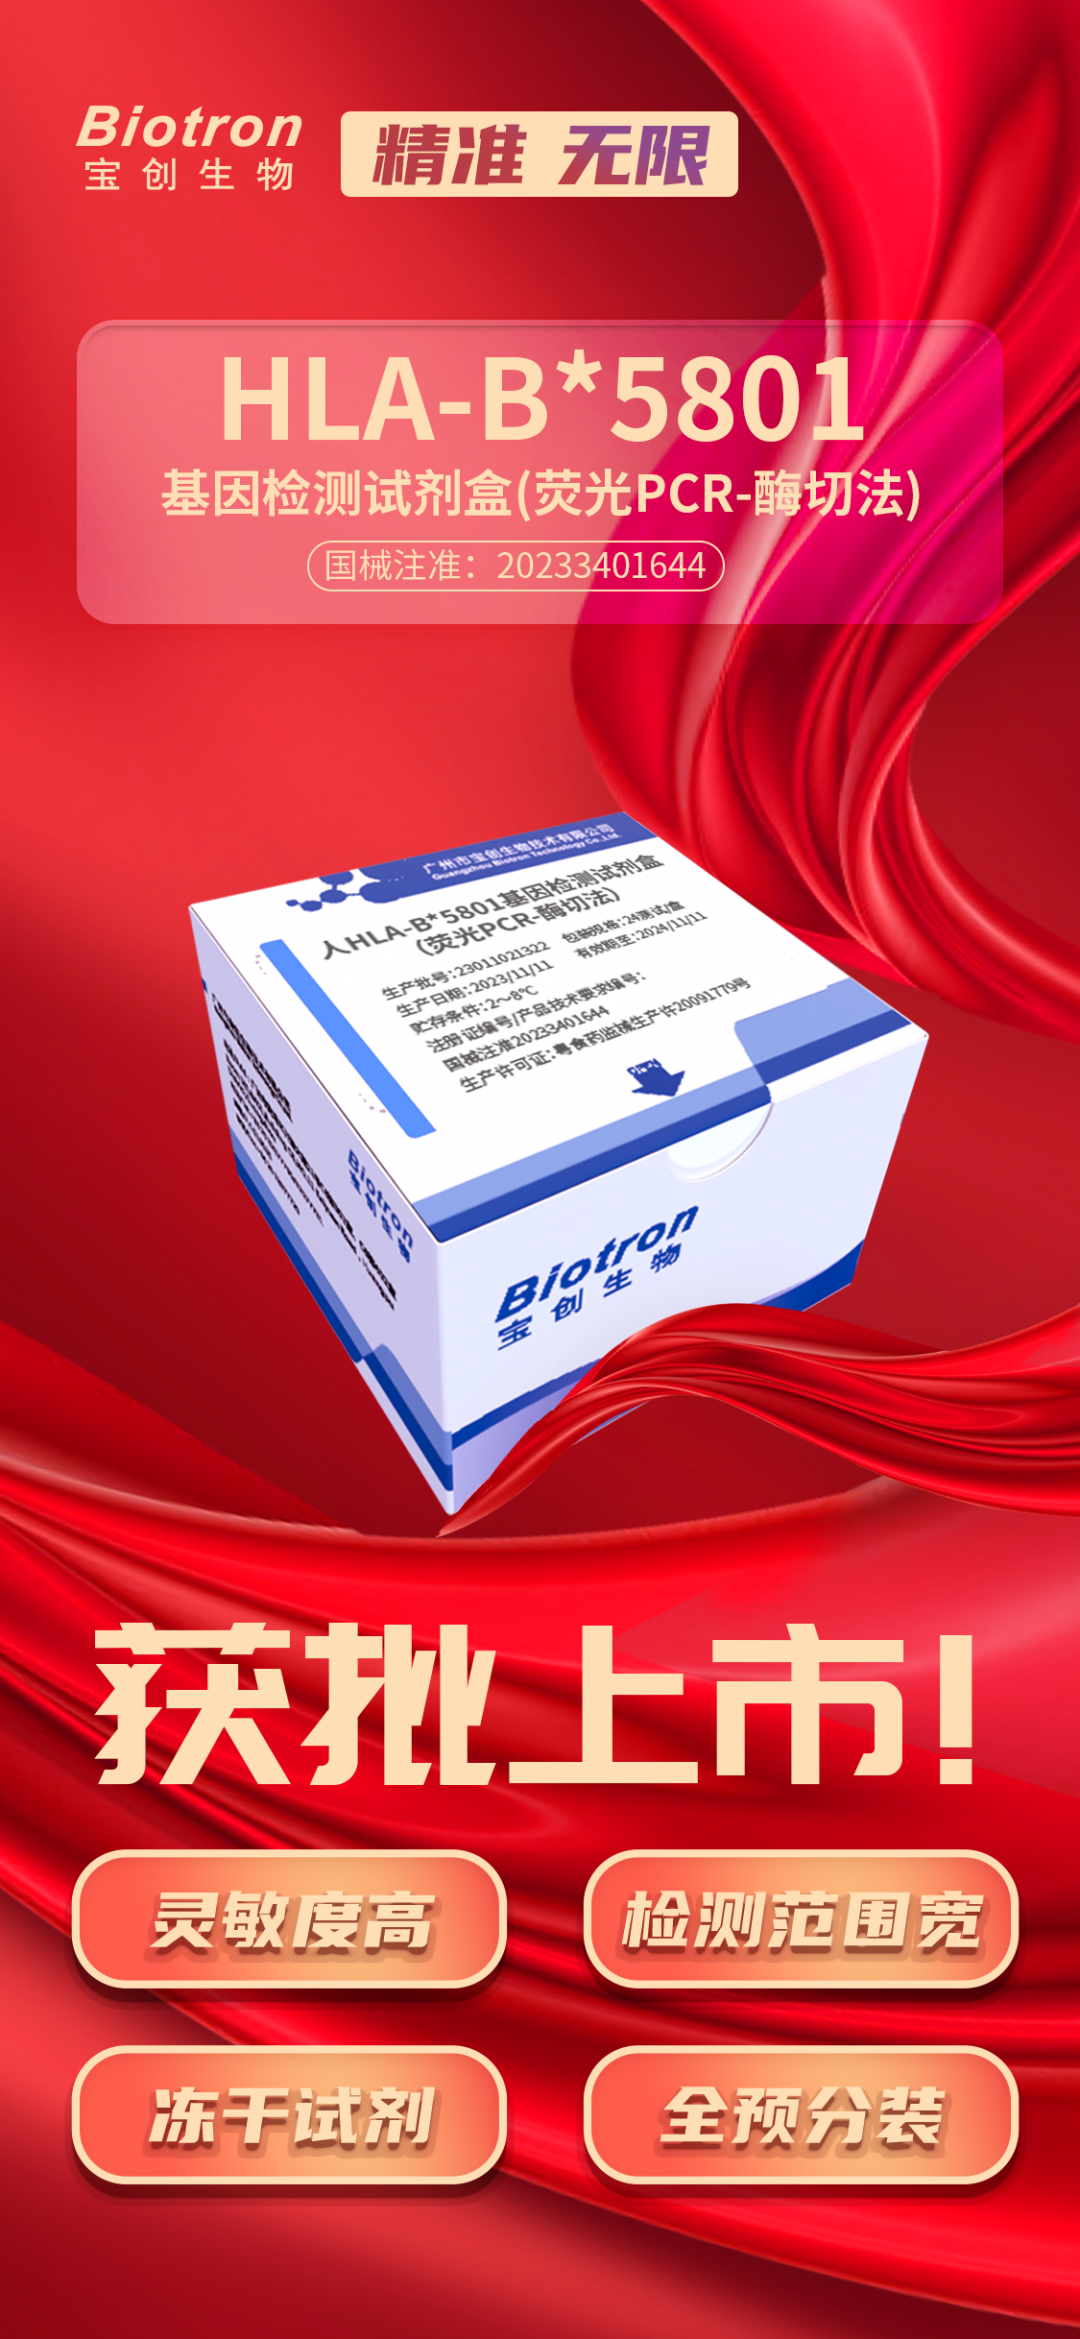

е…Ӣж—Ҙ�пјҢ�пјҢ�пјҢе®қ马bm1122зәҝи·ҜйЎ¶зә§з”ҹзү©пјҚдәәHLA-B*5801еҹәеӣ жЈҖжөӢиҜ•еүӮзӣ’пјҲиҚ§е…үPCR-й…¶еҲҮжі•пјүжӯЈејҸиҺ·еҫ—еӣҪ家иҚҜе“Ғзӣ‘и§ҶжІ»зҗҶеұҖпјҲNMPAпјүжҸӯжҷ“IIIзұ»еҢ»з–—еҷЁжў°жіЁеҶҢиҜҒпјҲжіЁеҶҢиҜҒеҸ·пјҡеӣҪжў°жіЁеҮҶ20233401644пјү�гҖӮ�гҖӮгҖӮгҖӮ